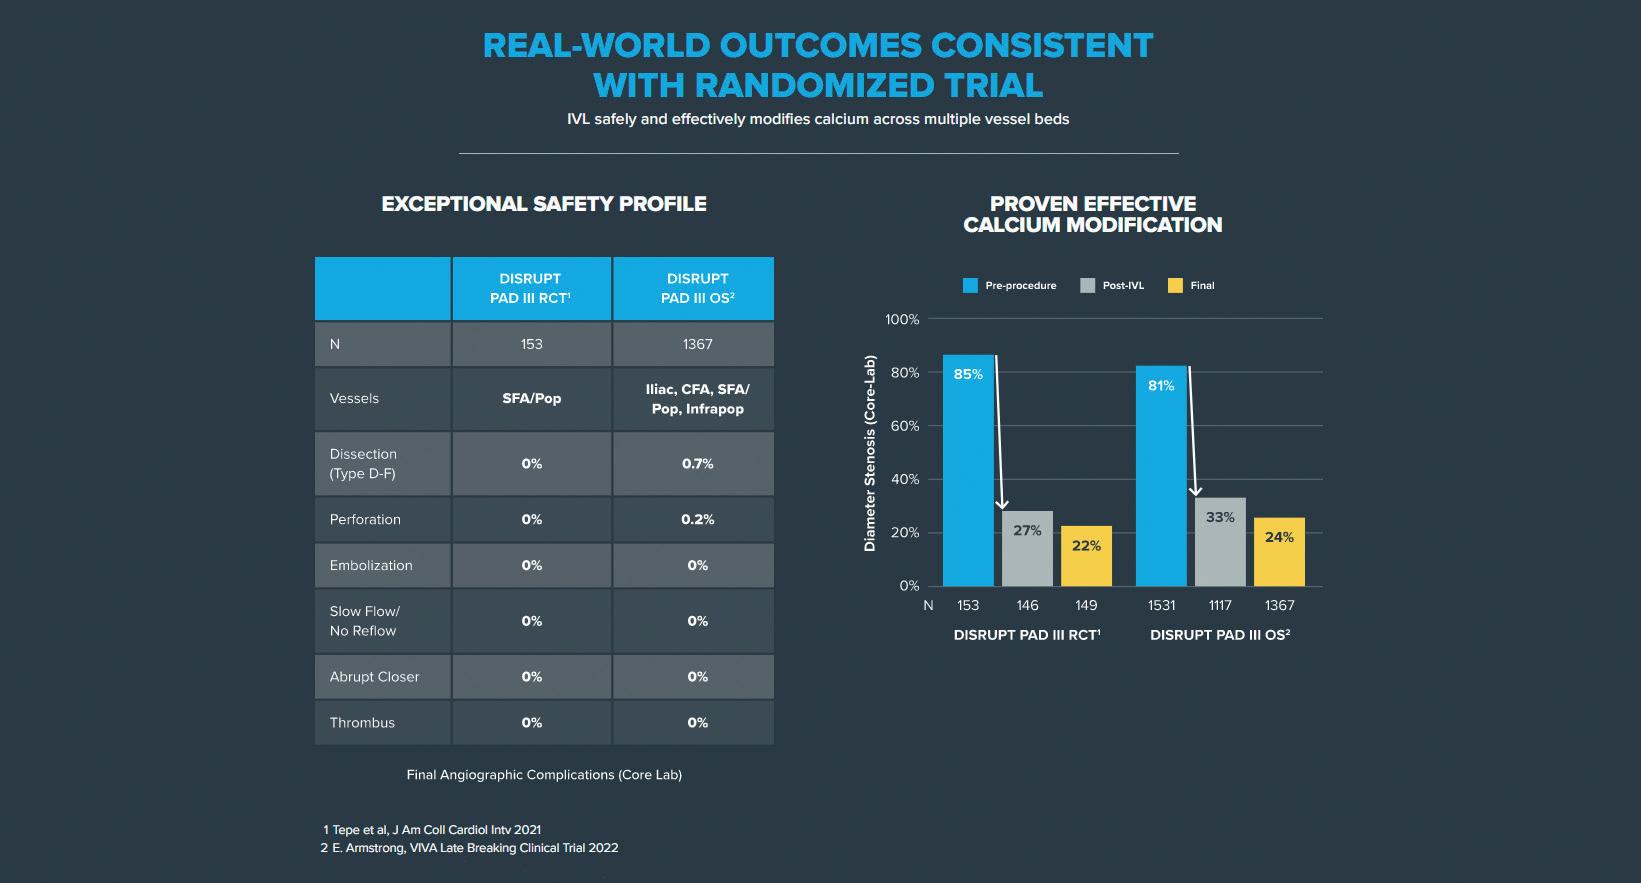

Despite being a relatively new tool, IVL has a growing data pool to back up the science with a randomised controlled trial (RCT) that demonstrated superiority in procedural success vs. conventional PTA in femoropopliteal lesions, with a reduction in complications and 75% reduction in the need for provisional stenting.4

The PAD III RCT demonstrated superior vessel preparation in an IVL group compared to a PTA group, with no complications (embolisations, perforations, thrombus, no flow), atraumatic treatment (max ballooning

pressure: 6.3 ATM vs. 11.3 ATM, p<0.0001), reduced dissections (type ≥C dissections: 3.5% vs. 15.1%, p=0.03) and bailout stenting (4.6% vs. 18.3%, p=0.0002).4

William A Gray and Gunnar Tepe, coprincipal investigators of DISRUPT PAD III, recently published two-year outcomes that confirm previous successful data: primary patency favoured IVL over PTA at one year (80.5% vs. 68%; p=0.017) and remained favourable through two years (74.4% vs. 57.7%; p=0.005).5

The PAD III RCT was reinforced by the PAD III observational study (OS)—a large all-comers registry that showed IVL to be an effective tool across all peripheral vessel beds, achieving consistently low residual stenoses and extremely low complications.6

The Disrupt PAD III OS with 1,373 patients and 1,677 lesions represents the largest prospective ‘real-world’ evidence for the treatment of heavily calcified PAD, and showed consistent outcomes with the randomised trial: an exceptional safety profile without final angiographic complications and proven effective calcium modification (residual final stenosis of 22% vs. 25%, PAD III RCT vs. OS, respectively).6,7

These optimal outcomes from the PAD III OS reinforce the predictability of IVL and

its ability to consistently modify calcium across multiple peripheral vessel beds (iliac, femoral, popliteal and infrapopliteal arteries), challenging lesions (severe calcification, chronic total occlusions, long [>15cm] and eccentric lesions) and complex patients (chronic limb-threatening ischaemia, dialysis, and female patients).